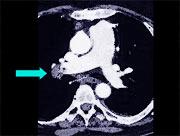

- 多项选择题患者男,突发胸部疼痛, 进行性呼吸困难1小时,行X线片检查, 提示右下肺病变,急诊CT平扫加增强, 如图所示 ( )

B、SCT增强扫描示右侧肺动脉主干完全性充盈缺损

C、右肺动脉开口处见不规则软组织密度影

D、考虑为右侧肺动脉(中央性)栓塞